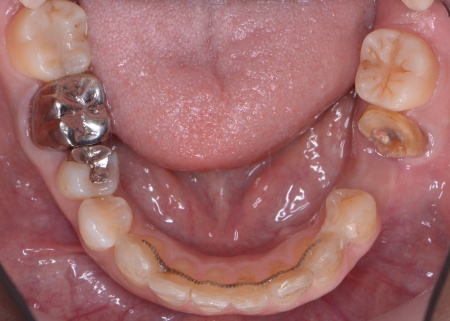

また、右の上下奥歯2本に装着されている白い被せ物や銀歯が劣化により歯に合わなくなり、虫歯の再発リスクが高まっていました。

さらに全体の噛み合わせを改善するため矯正治療を並行して行うこと、右上下奥歯の合わなくなった被せ物には矯正終了後に新しく作り直すこととしました。

①上あごの骨が狭く歯が並ぶスペースが不足しているため、まず上あごの骨の幅を広げる急速拡大装置を装着する。

成人になってからの骨の拡大は難しいものの、あごの骨に矯正用の小さなネジを埋め、そこを固定源として効率的に歯を動かす治療を併用することでスムーズに拡大を進める。

②①と並行して上下歯列にワイヤー矯正のマルチブラケット装置を装着し、歯並びと噛み合わせを整える。

④矯正終了後に右上下奥歯の合わなくなった被せ物を除去し、自然な白さで強度もあるジルコニアセラミッククラウンを装着する。

ワイヤー矯正、拡大装置、インプラント、骨造成、ジルコニアセラミッククラウン2本